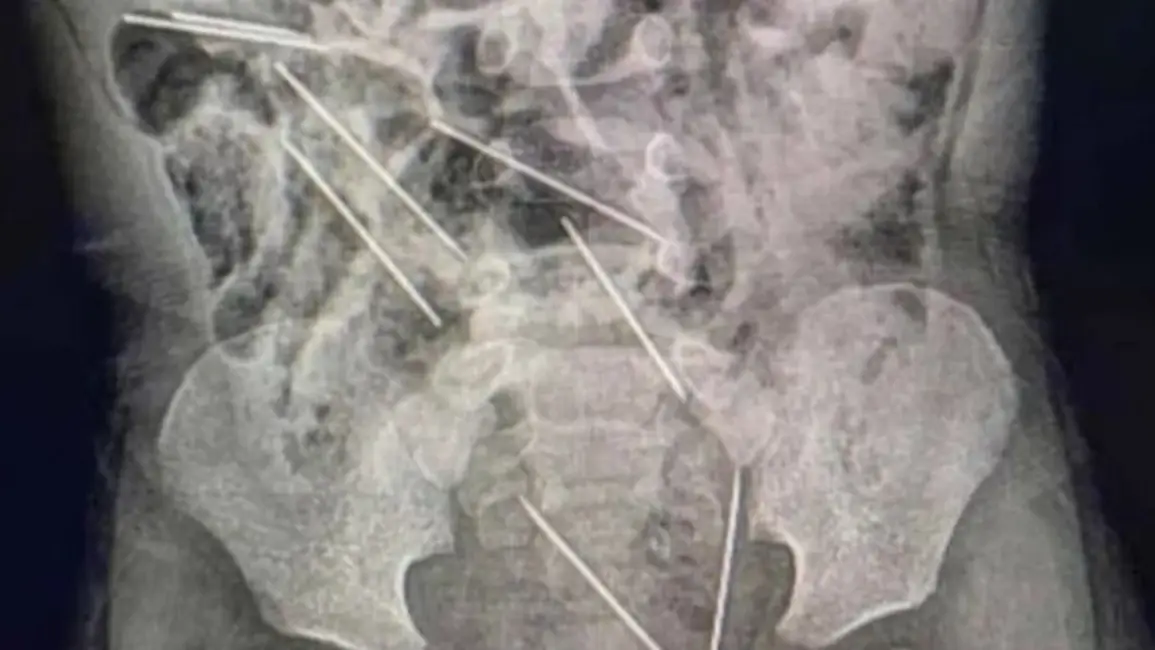

Los médicos le realizaron los estudios en los que detectaron la presencia de las agujas diversas partes de su cuerpo: dos en el peritoneo lado derecho, tres en el lado izquierdo, uno en la pared abdominal y las dos restantes entre la vejiga y el recto.